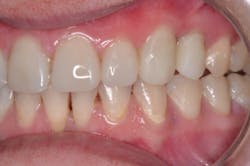

I knew Sarah when she was well and could smile at the world. Then, when the painful loss of a loved one dismantled her life, having no safety net or support, depression set in. Later, substance abuse took over, and eventually Sarah hit rock bottom. Thankfully, a local family took her in, and she is reclaiming her life. But her teeth and smile were devastated (figures 1 and 2).